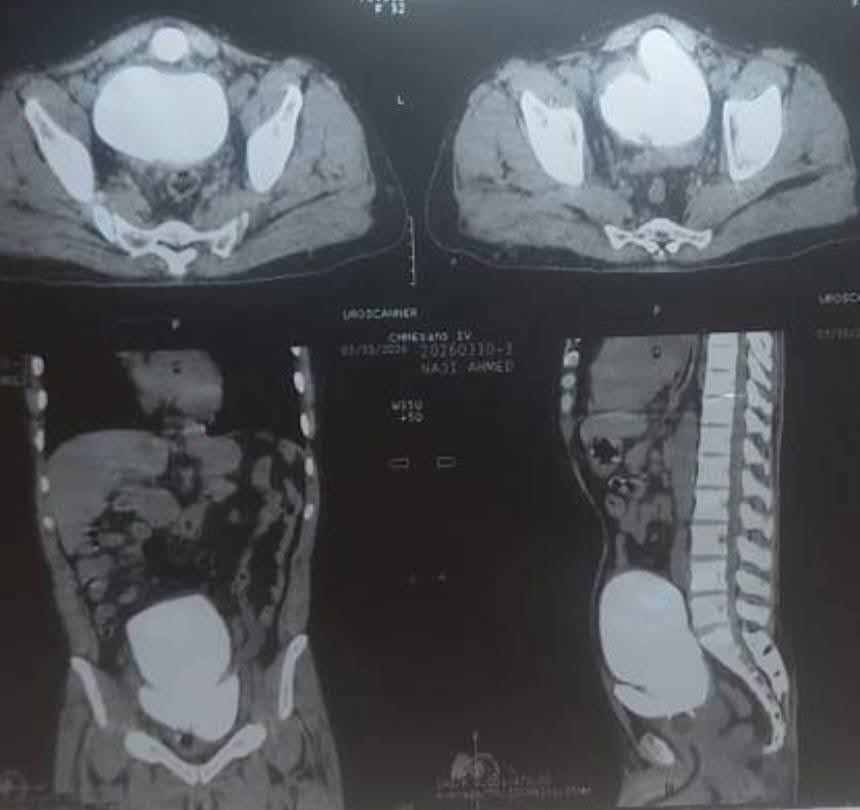

الأخبار (نواكشوط) – استأصل فريق طبي موريتاني بقيادة الأستاذ محمد المختار امباله حصاتي مثانة بمستشفى الصداقة بلغ وزنهما بعد الاستئصال 1500 غرام.

وقال الدكتور محمد الحسن البوساتي في منشور له على صفحته بالفيسبوك إن المريض الذي خضع لعملية الاستئصال وصل إلى المستشفى قادما من داخل البلاد.